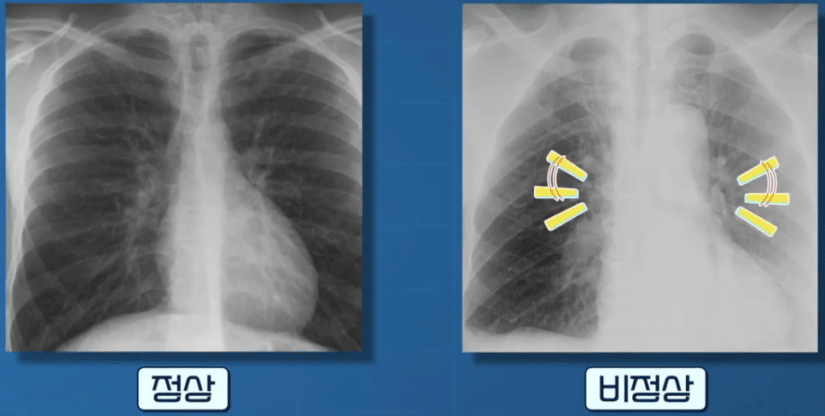

또 피떡은 폐 질환도 유발한다고 하는데, 피떡이 폐 혈관을 막을 경우 폐색전증이 발생할 수 있다고 하는데요.

폐색전증은 심부정맥에서 생긴 혈전이 이동하여 폐의 혈관을 막은 상태를 말하는데 호흡곤란부터 실신, 사망까지 이를 수 있는 질환이라고 합니다.